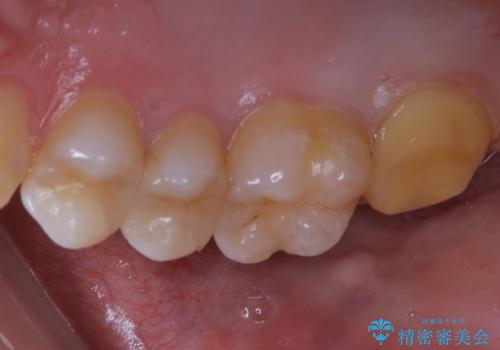

広範囲にわたる虫歯をセラミックで治療

痛み等の自覚症状はありませんでしたが、広範囲にわたる虫歯を認めたため、セラミッククラウンによる治療を行いました。

今回のケースでは、一番奥の歯の後ろ側に向かって虫歯が進行していました。一番奥の歯は元々の歯の高さが低いことが多く、被せ物が割れるリスクが増加したり、被せ物が外れやすくなる場合があります。歯牙切削量の少ないゴールドアンレーもご提案しましたが、セラミックをご希望されたため、今回はクラウンによる治療を行いました。